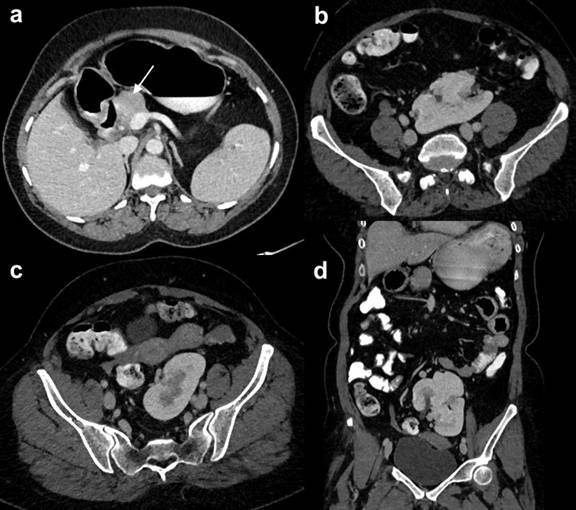

A forty five year old woman presented with intermittent pain abdomen in epigastrium and left hypochondrium for 6 months. USG abdomen revealed absent bilateral kidneys in renal fossa with midline fused kidneys in pelvis. CECT abdomen was performed for evaluation of kidneys which revealed pancake kidney with bicornuate uterus and dorsal pancreatic agenesis (Figure 1). Liver, gallbladder, common bile duct and spleen were normal. Blood glucose level was normal on repeated examinations (less than 90 mg/dL during fasting and 106 mg/dL postprandial) and urine showed pus cells on repeated examinations. However, urine culture was sterile. Exact cause of pain abdomen in this patient could not be found on imaging. So, she was advised to follow low fat diet and frequent light meals in view of possible cause of pain due to higher pancreatic duct pressure/enzyme hypersecretion or sphincter of Oddi dysfunction. She is short statured with short hand and fingers and left microphthalmia without any vision in left eye since birth. Patient has a male child diagnosed with congenital aplastic anemia likely Fanconi anemia and he is transfusion dependent since infancy. The child has facial anomalies and short fingers with bilateral cryptorchidism, however kidneys were normal.

Figure 1. Axial and coronal CECT images showing head and uncinate process of the pancreas (arrow) with non-visualization of neck, body and tail. Kidneys are located at the level of bifurcation of aorta in midline and they are fused suggestive of pancake kidney. |